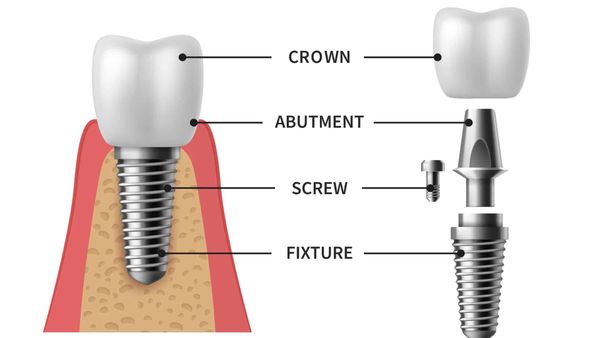

Cấu trúc của Implant bao gồm 3 phần là trụ Implant, Abutment và mão răng sứ, tương tự như một chiếc răng thật. Trong đó, trụ Implant là vật dụng có chất liệu được làm từ Titanium, có hình dạng trụ thuôn dần và được cố định vào xương hàm.

Cấu tạo của răng Implant gồm 3 phần là trụ, abutment và mão răng sứ

Trụ Implant được thiết kế giống như chân răng, có hình trụ hoặc dạng thuôn dần như đinh ốc, với bề mặt được xử lý đặc biệt để có khả năng tích hợp tốt với xương hàm. Quá trình cấy ghép được thực hiện sao cho trụ Implant không quá sâu, để không ảnh hưởng đến các mô mềm và hệ thần kinh, cũng không quá nông để đảm bảo độ chắc chắn. Sau một thời gian, trụ Implant tích hợp với xương, thay thế chân răng đã mất và làm trụ cho răng sứ hoặc cầu răng thay thế ở phía trên.

Trụ Implant có hình dạng giống như đinh ốc, có thể tương thích với xương hàm